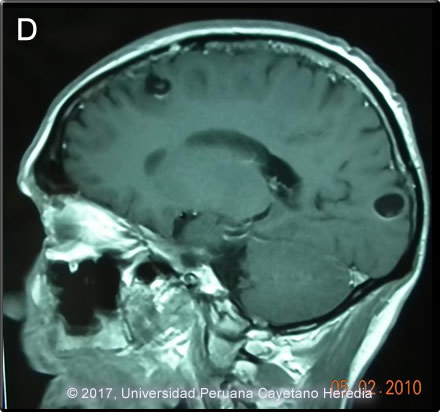

![]() Discussion:Diagnosis of neurocysticercosis can be problematic, especially in patients with one or 2 lesions. The imaging studies usually show cystic lesions (as in this case), but often do not demonstrate the scolex, which can be diagnostic. Studies in southern India of patients with single enhancing lesions were used to develop a clinical definition of cysticercosis. They found that, in patients with seizures, the combination of a single round lesion less than 2 cm in diameter with no midline shift, no symptoms or signs of other diseases, and a non-focal neurologic examination was highly predictive of neurocysticercosis. In a prospective study, this definition had a sensitivity of 99% and a specificity of 98.9% for cysticercosis [Rajshekhar V et al. Acta Neurol Scand 1987;96:76]. This definition has been incorporated into current guidelines for diagnosis [Del Brutto OH et. al. J Neurol SCi 2017;372:202]. Our patient had 2 lesions rather than 1, but they were clustered together and essentially met those criteria. The non-contrast CT scans are shown. Image A is s sagittal view that shows two cysts close to each other in the right occipital area without obvious edema. Image C is a coronal view that shows the two cysts lesions. While there is no definite scolex, the focal area of increased density on the edge of the cystic area suggests a scolex. The scolex is the head of the larval T. solium tapeworm. Typical viable lesions with scolex are shown in image D (from another patient). Cysticercosis is infection with the larval stages of the human pork tapeworm Taenia solium. Humans acquire cysticercosis after ingesting eggs of T. solium in material contaminated with feces originating in human tapeworm carriers. Humans that do not eat pork can get cysticercosis. Ingestion of contaminated pork results in humans getting an adult intestinal tapeworm – not cysticercosis. Cysticercosis is common in many developing countries and very common in rural agricultural areas of Perú. In developed countries, the long-lived cysticerci are increasingly seen as immigration from affected areas rises. Occasional transmission by tapeworm carriers to those who have never left non-endemic countries is reported. Ingested T. solium eggs hatch in the stomach and are then carried to the muscles and other tissues where the larvae encyst and reach their usual size of about 1 cm within a few months. Separate clinical, diagnostic, and therapeutic considerations apply to patients with the 4 forms of neurocysticercosis: intraparenchymal, ventricular, sub-arachnoid or spinal. See Gorgas Cases 2014-10, 2011-06, 2007-02, and 2006-04 for discussion of these presentations. The cysticerci seem able to evade the immune system and are thought to remain viable for several years without causing any inflammatory response, so that most infected patients are asymptomatic for years alter infection. Most clinical symptoms are the direct result of inflammatory responses that accompany the eventual cyst degeneration, but most patients likely remain asymptomatic even as cysts die. Epileptic seizures are the primary or sole clinical manifestation in up to 80% of symptomatic patients. In endemic regions new onset seizures in teenagers or young adults is most likely due to neurocysticercosis. Cysticerci can also cause symptoms because of mass effect, impingement on a vital structure or, especially if the cyst is intraventricular, blockage of CSF circulation. Patients with one or 2 parenchymal cysticerci have a relatively benign form of the disease. Even without specific treatment, the disease is usually self-limited. Based on that some clinicians had recommended not using antiparasitic treatment. However, the time course is often prolonged. Two meta-analyses of randomized trials have been published on treatment of patients meeting the definition of solitary cysticercal granulomas [Zhao BC et al. PLoS Neg Trop Dis 2016;10(2):e0004418; Otte WM et al. Neurology 2013;80:152] . Overall, the radiographic resolution is more rapid and the number of seizures during the 6 months after diagnosis is improved in patients treated with a short course of albendazole and corticosteroids (typically 1-2 weeks). However, that treatment did not decrease the proportion of patients who subsequently developed calcifications on CT scan and did not impact the frequency of seizure more than 6 months after presentation. Interestingly, most patients with a single lesion resolve without forming calcifications. In those with few seizures and radiographic resolution (which usually occurs within 6 months of albendazole treatment), anti-epileptic drugs can safely be tapered off. Parenchymal neurocysticercosis with more than 2 viable and/or degenerating cysts should be treated with Albendazole 15 mg/kg per day (max. 800 mg/day) + Praziquantel 50 mg/kg per day + Dexamethasone 0.1 mg/kg/day beginning 1 day prior to anti parasitic drugs] x 10 days ± Anti-seizure medication if needed [Garcia HH et. al. Lancet Infect Dis 2014;14:687]. Some data suggest that higher doses of corticosteroids may decrease early seizures. Albendazole alone without praziquantel is likely adequate if only 1-2 cysts on an MRI. Dead, calcified cysts only require no antiparasitic treatment. Our patient responded rapidly to albendazole and steroids. |